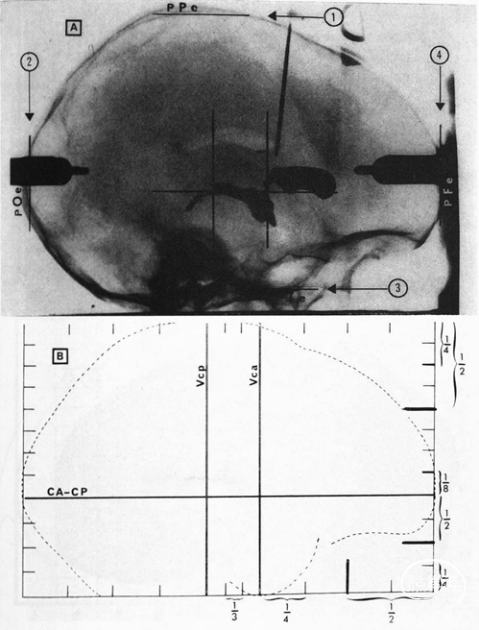

脑室造影塔莱拉什坐标空间(上图);比例网格系统(下图)

1988年,塔莱拉什和皮埃尔·图尔努(Pierre Tournoux)共同出版了第三本涵盖了整个人类大脑的图集。认识到患者之间的神经解剖学差异,他们发明了一个比例网格系统,使塔莱拉什空间中的任意点都能转换到患者特定的坐标空间中,反之亦然。塔莱拉什认为比例网格系统的发展是一个完整立体定位系统的必要组成部分,主要有两个原因。首先,比例网格系统的加入允许考虑整个大脑的体积,而立体定位系统只关注深灰色核团或孤立地关注颞叶,例如,每个系统都有各自的参考点系统。而全脑立体定位系统是必要的,特别是SEEG工作中。其次,比例网格系统允许立体定位系统超越神经外科干预对个体的指导,它为跨个体的功能定位研究提供了一个可行的工具,使得任何个体特定的点都可以抽象到一个标准化的空间中。由于他在立体定向方面的突出贡献,塔莱拉什于1989年被法国科学院(Académie des Sciences)授予了化学和自然科学大奖。

1957年,塔莱拉什及其同事利用立体定位仪,通过研究100具尸体的大脑,成功得出第一套人类深灰色核团的立体定向图谱。尽管在霍斯利和克拉克等使用的动物立体定位图谱中,颅骨标志的使用是金标准,但是颅骨标志作为间接定位的参考标准而言被认为不够可靠,不仅因为误差容限较低,而且人类之间的结构差异比实验室动物之间的结构差异更大。塔莱拉什引入了前连合(anterior commissure,AC)和后连合(posterior commissure,PC)作为标准参照点,因为这些参考点可以在对比脑室造影中可靠地识别出来,并且非常接近深灰核团。由此催生了塔莱拉什坐标空间,即由AC的原点、AC-PC线的Y轴以及从AC开始分别沿水平面和垂直线垂直延伸的X轴和Z轴构成。1958年,塔莱拉什荣升圣安妮医院新成立的立体定位和功能神经外科服务部门的负责人,在这里,他与匈牙利神经外科医生伽柏·西拉德(Gábor Szikla)一起,创建了第二本聚焦端脑的图集。